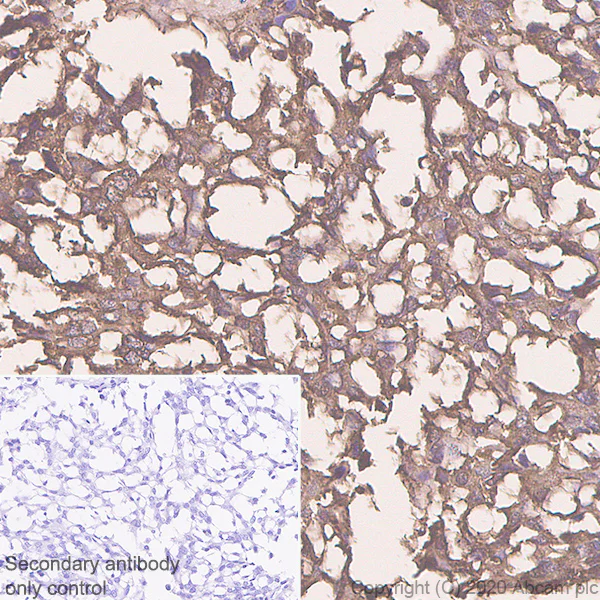

Immunohistochemistry (Formalin/PFA-fixed paraffin-embedded sections) - Anti-Procalcitonin antibody [4A6] - BSA and Azide free (AB255777)

Immunohistochemical analysis of paraffin-embedded human thyroid medullary carcinoma tissue labeling Procalcitonin with ab252821 at 1/1000 dilution followed by a ready to use Goat Anti-rat IgG H&L (HRP polymer) (ab214882). Positive staining on human thyroid medullary carcinoma. The section was incubated with ab252821 for 30 mins at room temperature. The immunostaining was performed on a Leica Biosystems BOND® RX instrument. Counterstained with Hematoxylin.

Secondary antibody only control : Secondary antibody is a ready to use Goat Anti-rat IgG H&L (HRP polymer) (ab214882).

Heat mediated antigen retrieval with Tris-EDTA buffer (pH 9.0, epitope retrieval solution2) for 20 mins.

This data was developed using the same antibody clone in a different buffer formulation containing PBS, BSA, glycerol, and sodium azide (ab252821).